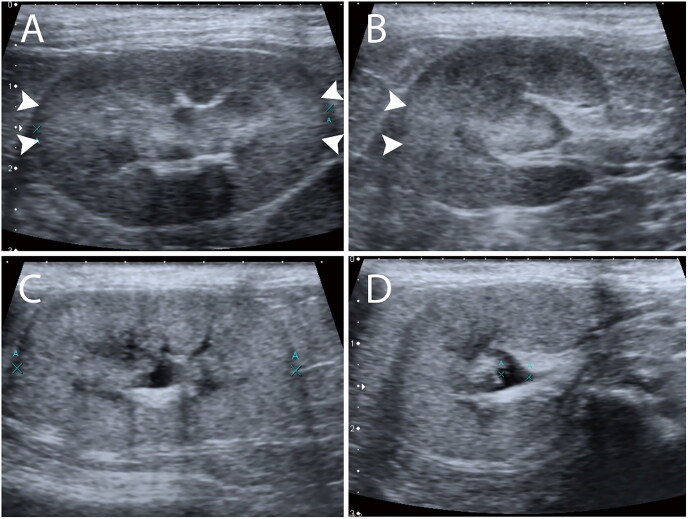

利用超声波检查猫氮质血症临床结果的信息非常有限。本研究旨在了解猫科动物氮质血症住院后皮质各向异性反向散射伪影(CABA)与血清肌酐(sCr)变化之间的相关性,并探讨CABA是否有助于预测猫科动物氮质血症的临床结果。65 只患有氮质血症的住院猫,其中 49 只患有中度或重度氮质血症(重度组),16 只患有轻度氮质血症(轻度组)。这项回顾性研究利用 2016 年至 2021 年期间因氮质血症住院的猫的超声波图像回顾了 CABA。采用卡方检验(chi-squared)或费雪精确检验(Fisher's exact)研究了CABA与氮质血症猫临床结果之间的相关性,并采用麦克尼玛检验(McNemar's)和科恩卡帕检验(Cohen's kappa)评估了CABA的观察者内部和观察者之间的一致性。只有在严重组中,CABA的存在与氮质血症猫的临床结果呈显著正相关(p = 0.0034,几率比 = 8.57)。轻度氮质血症猫的 CABA 与临床结果没有关联(p = 0.75)。CABA 可用于预测中度和重度氮质血症猫的临床结果,灵敏度为 80.8%,特异性为 73.9%。此外,在超声图像审查期间检测 CABA 时,观察者内部和观察者之间的一致性也令人满意。我们的研究表明,中度和重度氮质血症且在超声波检查中观察到CABA的猫可能会有更好的临床预后。这些发现为猫氮质血症的预后和治疗提供了更多信息。

Information on the clinical outcomes of feline azotemia using ultrasound examinations is limited. This study aimed to understand the correlation between cortical anisotropy backscattering artifact (CABA) and serum creatinine (sCr) changes in feline azotemia after hospitalization and to investigate whether CABA is useful for predicting the clinical outcome of feline azotemia. Sixty-five hospitalized cats with azotemia, including 49 cats with moderate or severe azotemia (severe group) and 16 cats with mild azotemia (mild group). This retrospective study reviewed the CABA using ultrasound images of cats hospitalized with azotemia between 2016 and 2021. The correlation between CABA and the clinical outcomes of cats with azotemia was investigated using the chi-squared or Fisher's exact test, and the intra- and inter-observer agreements in CABA were assessed using McNemar's and Cohen's kappa tests. The presence of CABA was significantly positively correlated with the clinical outcomes of cats with azotemia only in the severe group (p = 0.0034, odds ratio = 8.57). There was no association between CABA and clinical outcomes in cats with mild azotemia (p = 0.75). CABA can be used for clinical outcome prediction in moderate and severe feline azotemia, with a sensitivity of 80.8% and a specificity of 73.9%. Also, satisfactory intra- and inter-observer agreements were revealed in the detection of CABA during ultrasound image review. Our study demonstrated that cats with moderate and severe azotemia with CABA observed during ultrasonography might have better clinical outcomes. These findings provide additional information on the prognosis and treatment of feline azotemia.